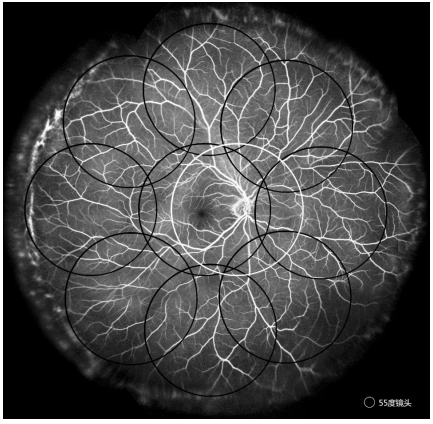

4) 使用45°、55°或更大角度镜头进行FFA检查拍摄范围应尽可能包含后极部和周边八方位(图2);可根据需要变动方位,如以病灶为圆心拍摄,或向更周边部移动(需要患者眼位和造影仪采集头同时转动配合)。超广角镜头拍摄范围应尽可能涵盖全视网膜。

以55°镜头为例在全视网膜FFA拼图中显示后极部和常规周边共9方位大体拍摄位置(黑环),白环显示以视盘颞侧缘为圆心的拍摄方位。

The montage demonstrates the general imaging positions (black circles) of the posterior pole and conventional peripheral retina across nine orientations using a 55° lens. The white circles indicate imaging orientations centered on the temporal edge of the optic disc.

图2 55°镜头为例的全视网膜FFA拼图

Figure 2 Montage of pan retinal FFA using a 55° lens